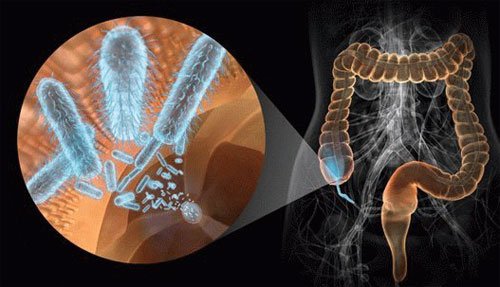

Микробиота кишечника (нормофлора, микрофлора) – это совокупность микроорганизмов, которая является обязательной составляющей нормальной жизнедеятельности человеческого организма. Присутствие микробов в кишечнике человека...